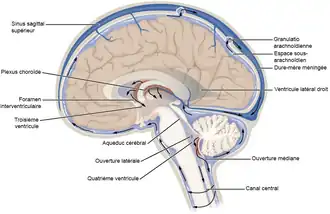

Le liquide cérébrospinal (LCS), ou liquide céphalo-rachidien (ou céphalorachidien) (LCR) en ancienne nomenclature, est un liquide biologique transparent dans lequel baignent le cerveau et la moelle spinale. Il est contenu dans les méninges, plus précisément entre la pie-mère (qui recouvre le système nerveux central) et l'arachnoïde (qui tapisse le versant interne de la dure-mère), c'est-à-dire dans l'espace sous-arachnoïdien. C'est également le liquide qui circule dans les quatre ventricules cérébraux, à l'intérieur du cerveau, dans le canal central de la moelle spinale puis au-delà du tube neural jusqu'au cul-de-sac dural.

Il est sécrété par les plexus choroïdes au niveau des ventricules latéraux, ventricule 3 et ventricule 4 dans les hémisphères cérébraux dérivant du tube neural encéphalique primitif.

Le LCS circule librement dans le système ventriculaire et les méninges, à travers un circuit continu et ne présente pas de poche isolée de liquide en stagnation, passant par les trous de Monro pour aller dans le 3e ventricule, traversant ensuite l'aqueduc de Sylvius pour arriver dans le 4e ventricule. De là, deux possibilités s'offrent à lui : soit il descend autour de la moelle spinale, soit il sort par l'ouverture médiane de Magendie et les trous de Luschka au niveau du toit du 4e ventricule pour passer dans l'espace sous-arachnoïdien.